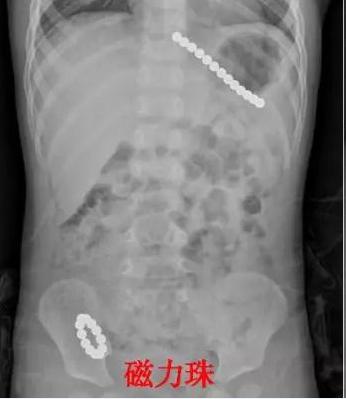

戒指、耳钉、干电池、绣花针、磁力珠、小木棒、拉链、螺丝钉……这些比较罕见的,也都是山东大学齐鲁医院(青岛)近几年接诊的消化道异物患儿中发现的。

来,眼见为实。